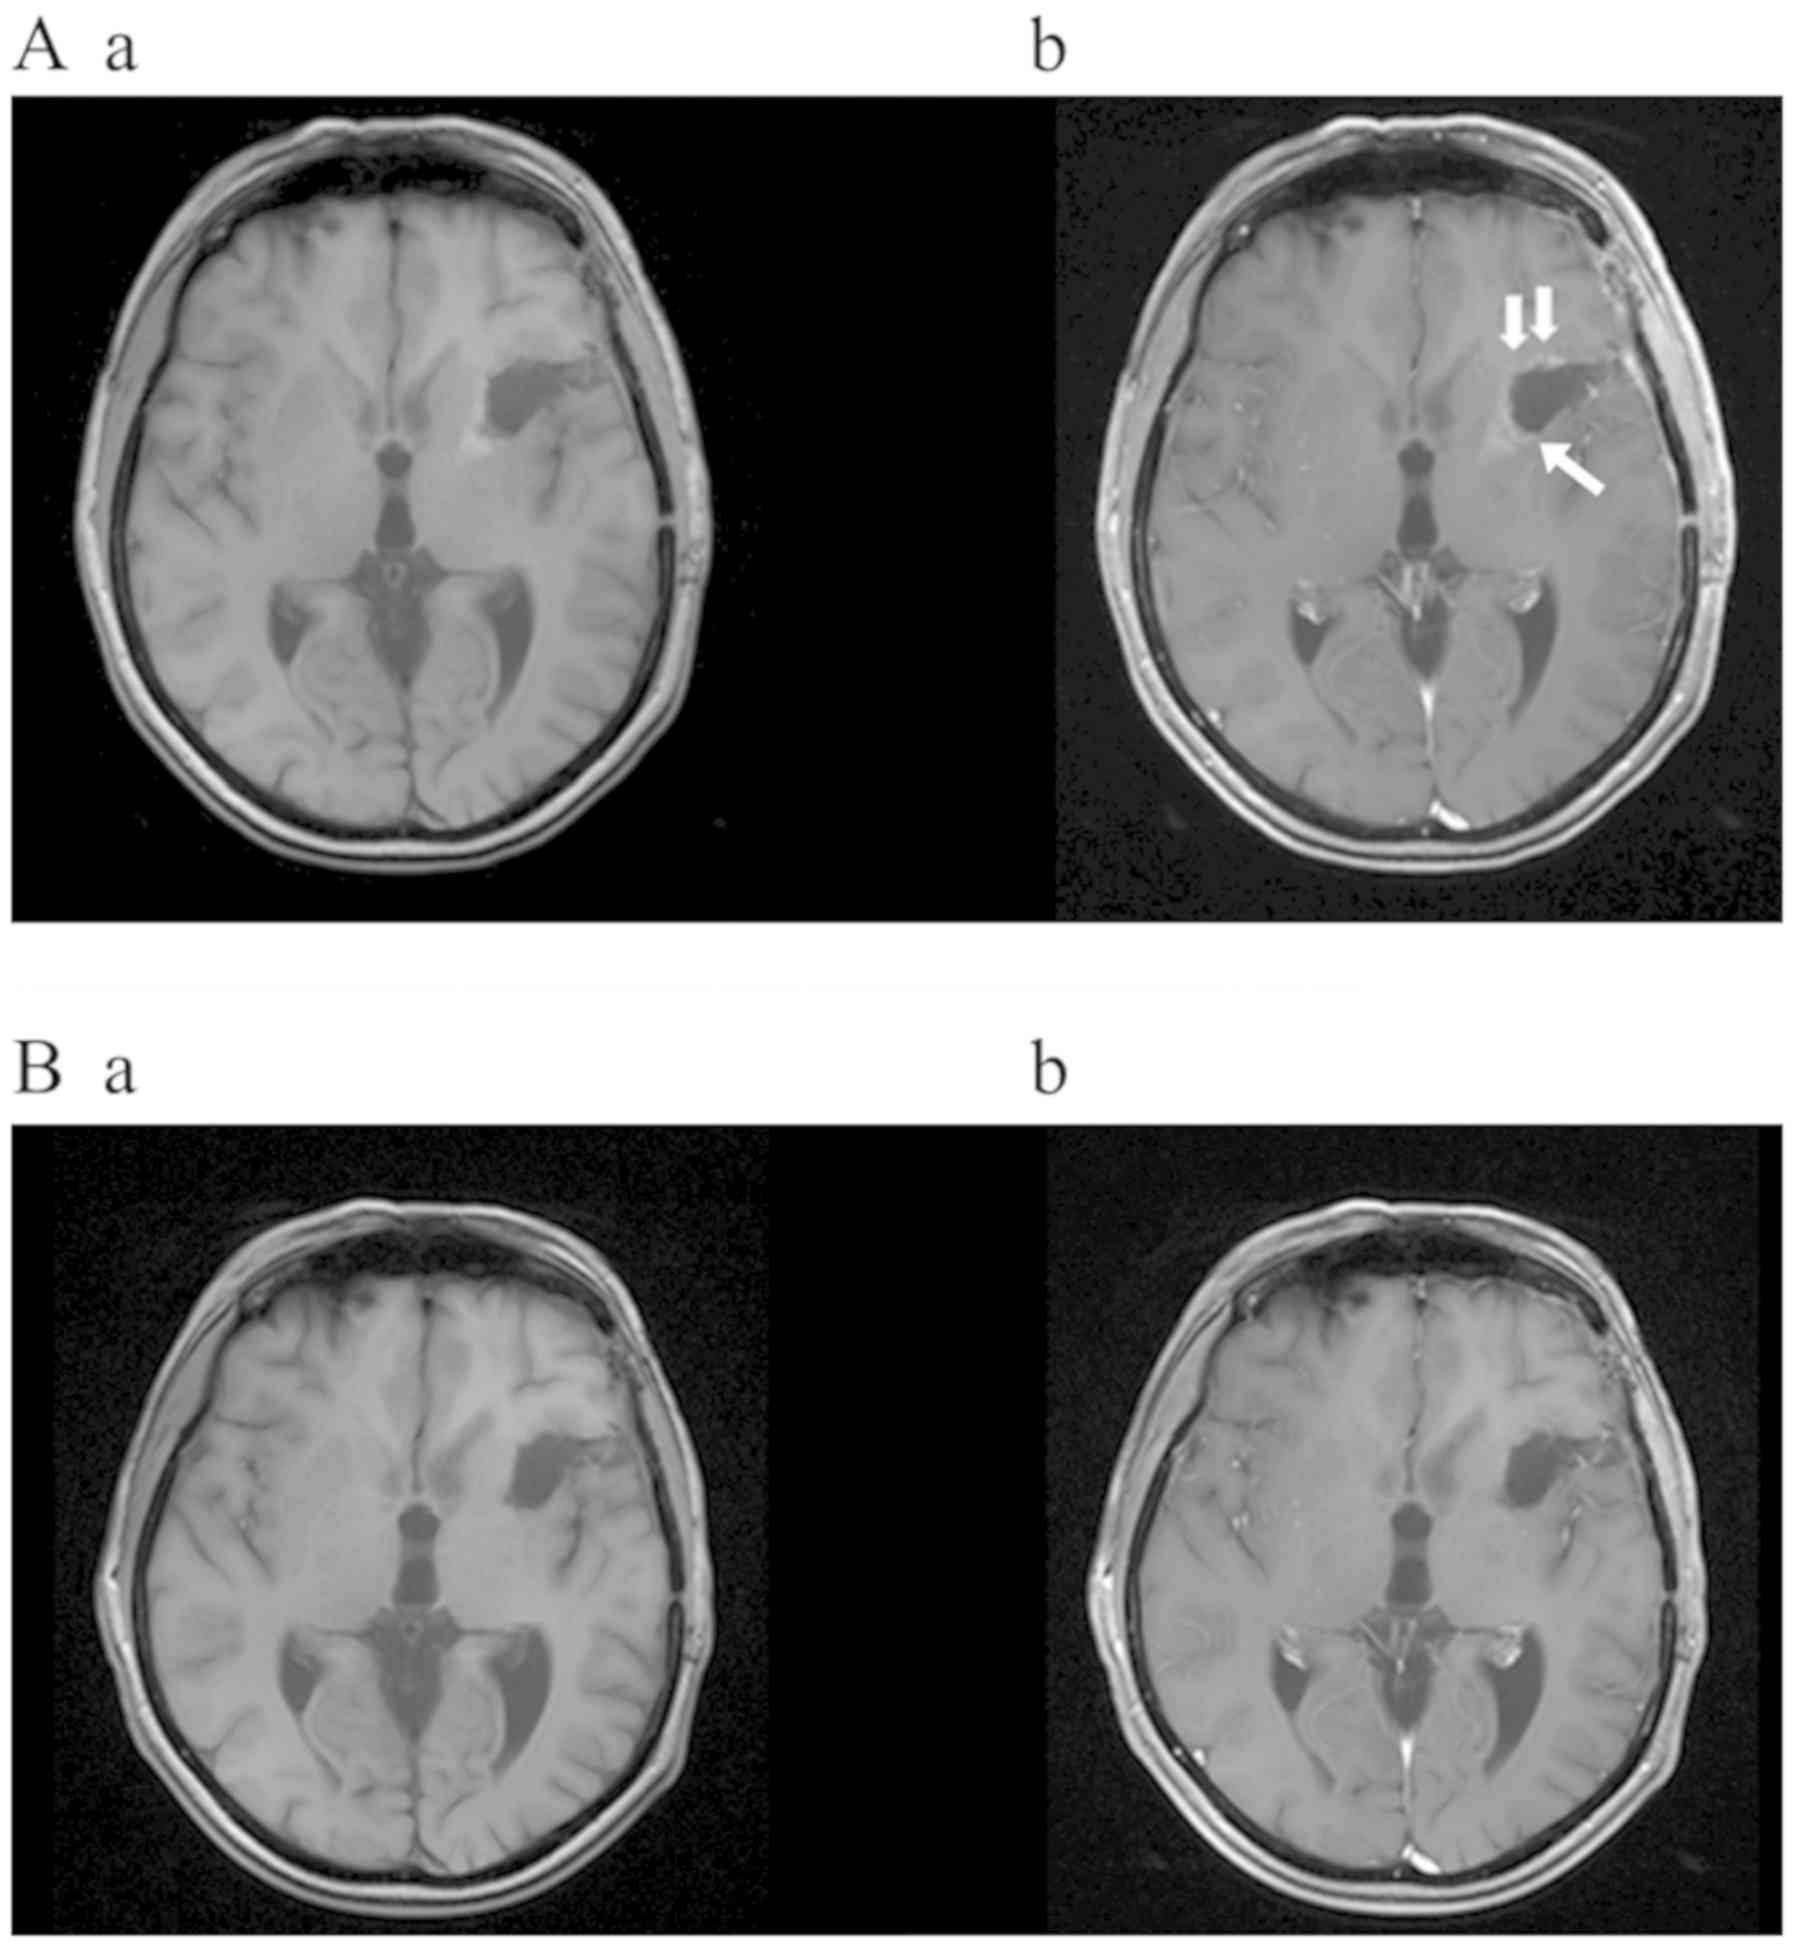

Patient three (male, 44 years, KPS 100%) presented with seizures. The MRI showed a right frontal lesion involving parts of the corpus callosum. The FET-PET scan revealed a maximal tumor-to-background ratio (TBR) in the right anterior middle frontal gyrus. Early postoperative MRI showed residual tumor tissue at the margins of the resection cavity. Histopathology confirmed anaplastic astrocytoma WHO grade III. Subsequent irradiation therapy was administered up to 61.2 Gy with concomitant daily TMZ (75 mg/m2). After 4 cycles of adjuvant TMZ, a follow-up MRI revealed a progression of the contrast enhancing lesion at the inferior margin of the resection cavity and the corpus callosum, which was identified as a true tumor recurrence by a FET-PET scan. After repeated surgery, the early postoperative MRI presented a contrast enhancing tumor residue at the inferior margin of the resection cavity (Fig. 3A), extending into the genu of the corpus callosum (Fig. 3B) due to the subtotal resection. Histopathological workup revealed GBM WHO grade IV (methylated MGMT promoter, IDH1 R132H mutation). Due to the presence of methylated MGMT-promoter, TMZ therapy was resumed for another 6 cycles. In addition, TTFields treatment was initiated at cycle 4. During the first period of the TTFields treatment, the patient started at a compliance rate of ~75%. Interestingly, 6 months after surgery, the cranial MRI displayed a distinct regression of the contrast enhancement in the corpus callosum. Another 3 months later, no contrast enhancing tumor residues were discernible, which continued for 40 months after the second resection and until the end of the follow-up period (Fig. 3C and 3D). Simultaneously, the patient reported a high quality of life (QoL) and active participation in his Martial Arts training sessions as well as travel activities to foreign countries. Although suffering from psoriasis of the arms, legs and scalp, being treated with urea-based lotion and intermittendly with cortisol-based lotion, there were no adverse events besides mild skin irritation, no seizures or neurological abnormalities. The patient is working full-time and is permanently using the TTFields therapy with an average compliance of around 60% before terminating TTFields application after 37 and 40 months after STR up to the end of observation period.

Figure 3.

Coronal MRI of patient three (male; 44 years old) before (Aa/Ba/Ca/Da) and after (Ab/Bb/Cb/Db) gadolinium application. Early post-surgery MRI (48 h after surgery) was completed following the second STR with contrast enhancement in the marginal zone of the resection cavity (A) extending to the corpus callosum (B) (C) Images obtained from the same patient after another 6 cycles of Temozolomide and (D) 37 months of Tumor Treating Fields treatment (35 months as monotherapy). The patients presents complete response of the postoperative tumor residue 40 months after STR. STR, subtotal resection.